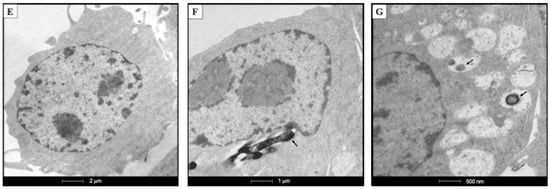

4.9. TEM